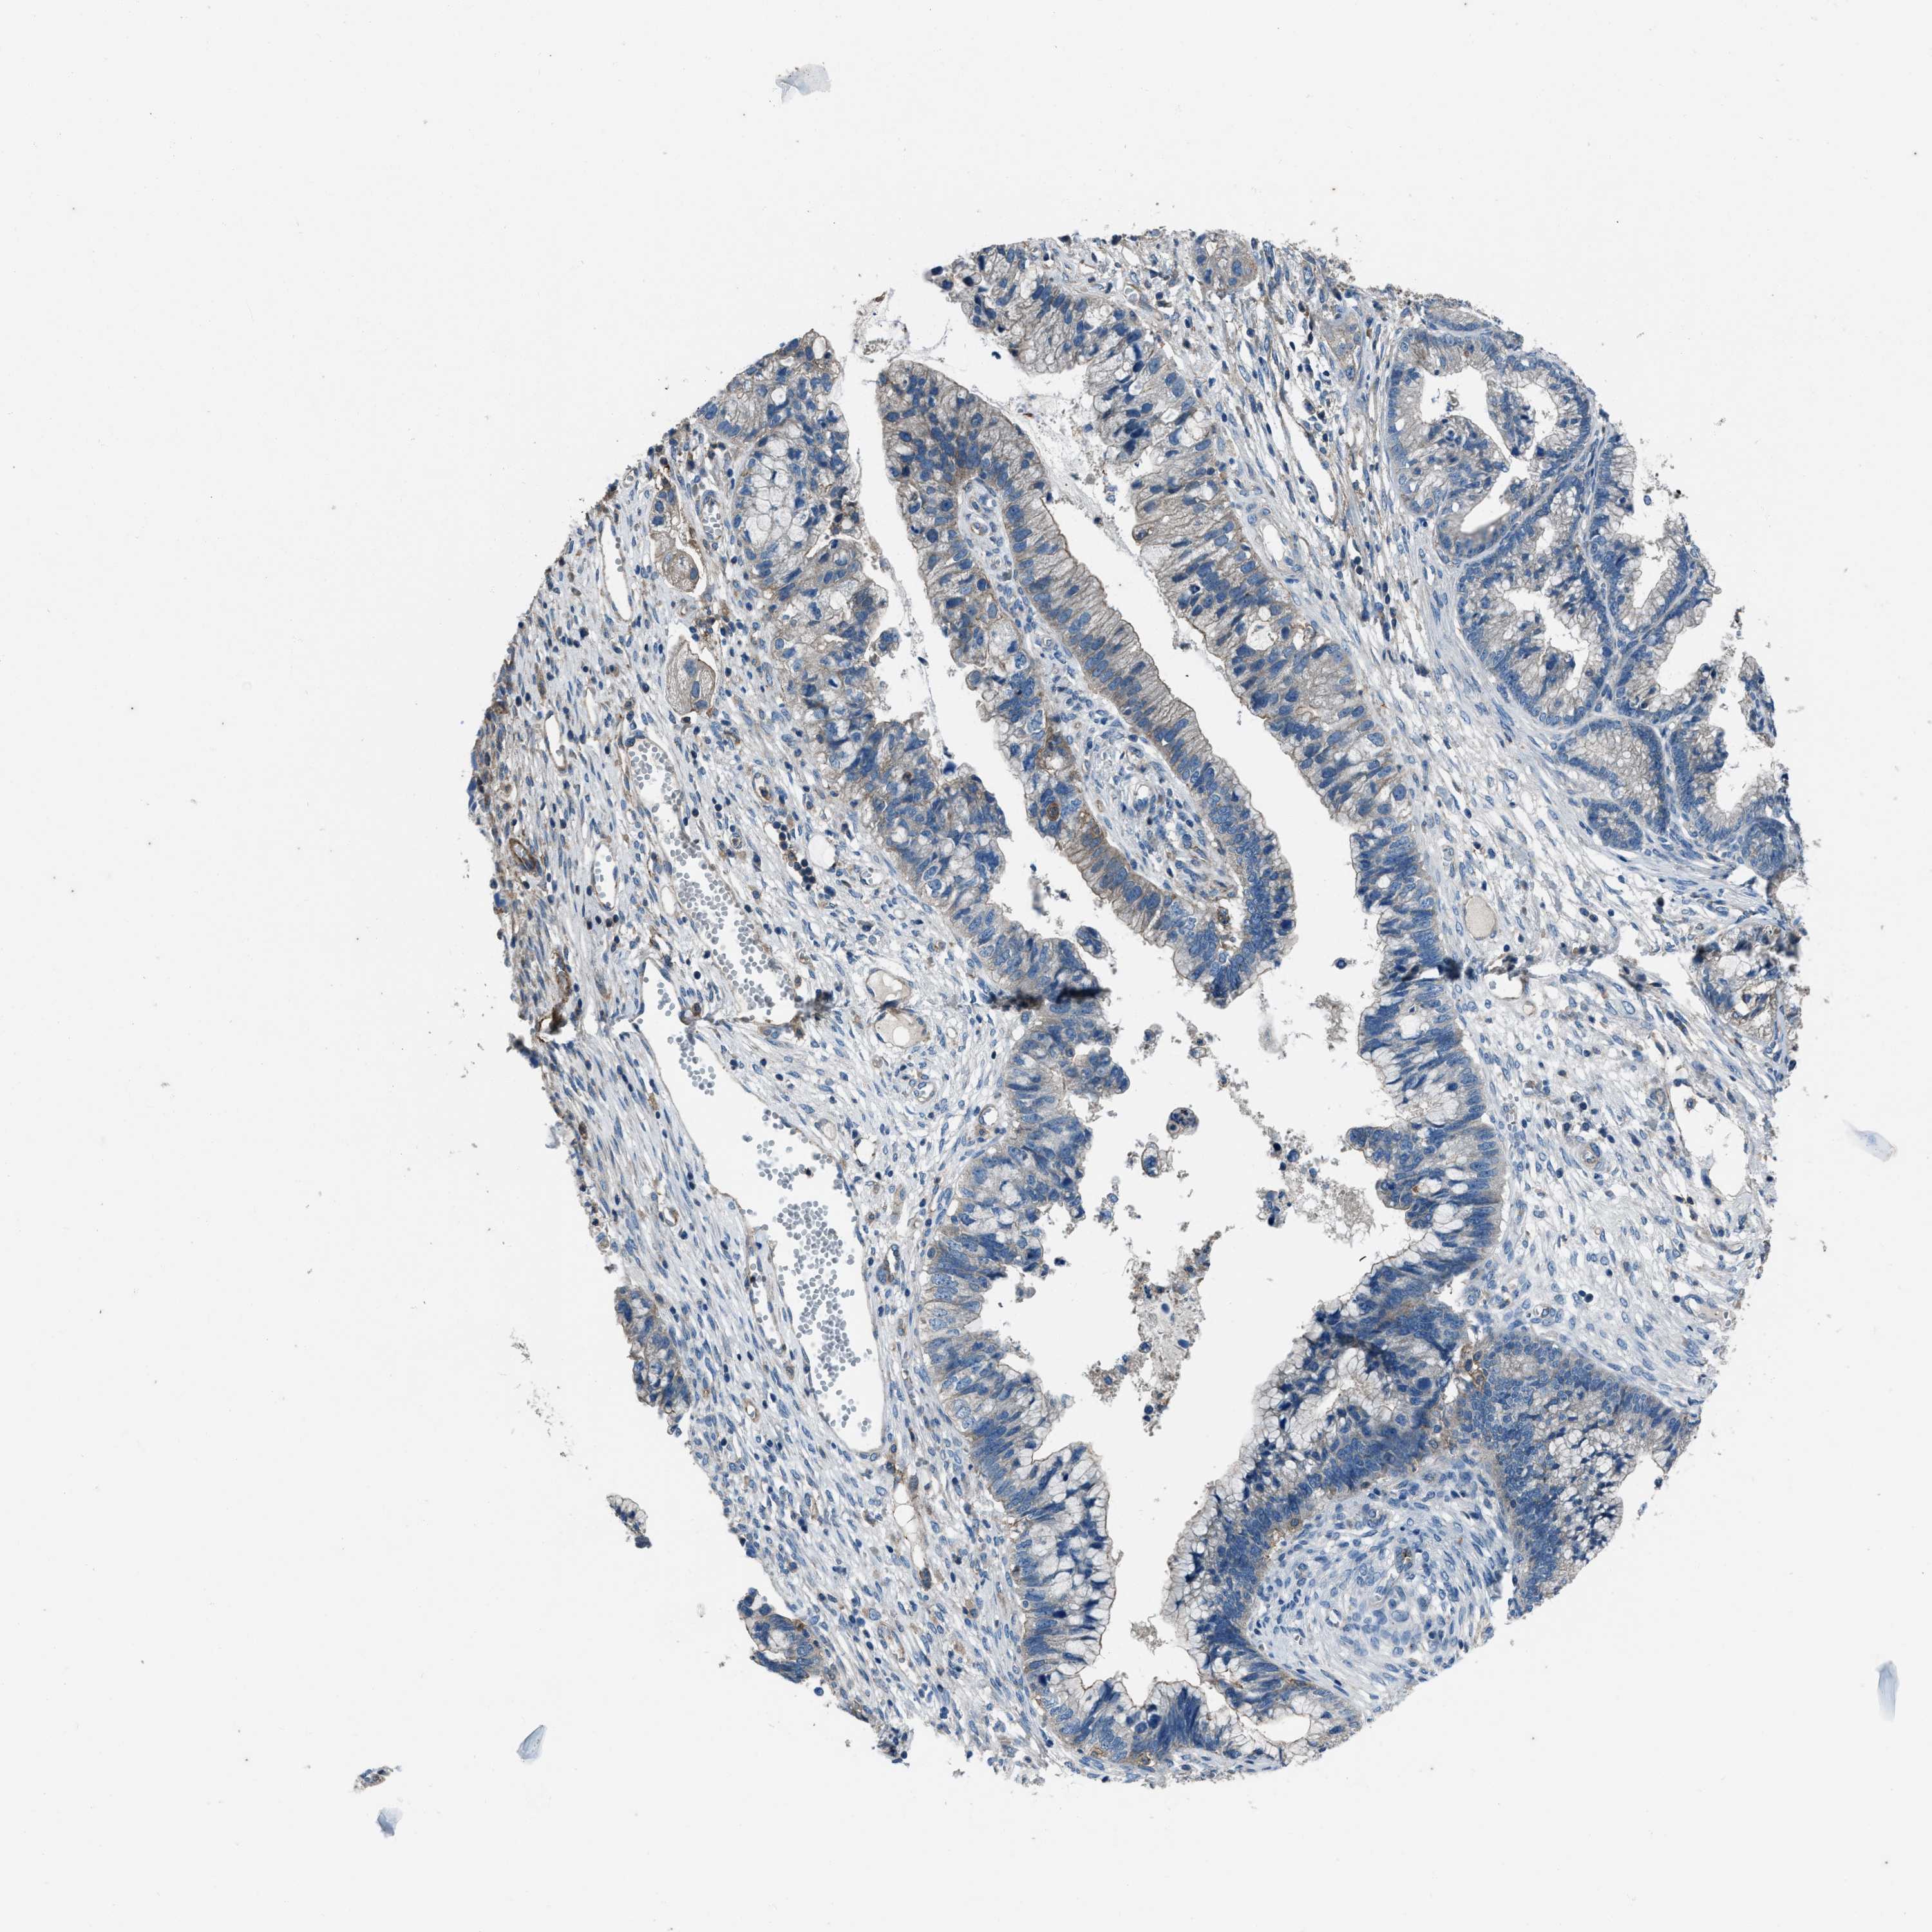

CERVICAL CANCER - Protein expressioni

A mouse-over function shows sample information and annotation data. Click on an image to view it in a full screen mode. Samples can be filtered based on level of antibody staining by selecting one or several of the following categories: high, medium, low and not detected. The assay and annotation is described here.

Note that samples used for immunohistochemistry by the Human Protein Atlas do not correspond to samples in the TCGA dataset.

Antibody stainingi

Antibody staining in the annotated cell types in the current human tissue is reported as not detected, low, medium, or high, based on conventional immunohistochemistry profiling in selected tissues. This score is based on the combination of the staining intensity and fraction of stained cells.

Each image is clickable and will lead to virtual microscopy that enables deeper exploration of all samples and also displays staining intensity scores, fraction scores and subcellular localization as well as patient and tissue information for each sample.

Antibody HPA020095

Antibody HPA020138

Antibody CAB010878

Antibody CAB080402

Adenocarcinoma, NOS